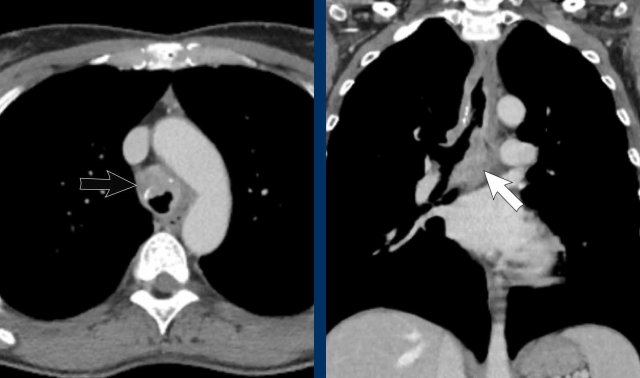

Image

Right-sided fibrosing mediastinitis in a 51 year old male, showing soft tissue density around the right main bronchus (arrow).

Same patient.

There are secondary signs of central airway and vessel

compression, with localized lung volume loss and interstitial thickening due to

edema.